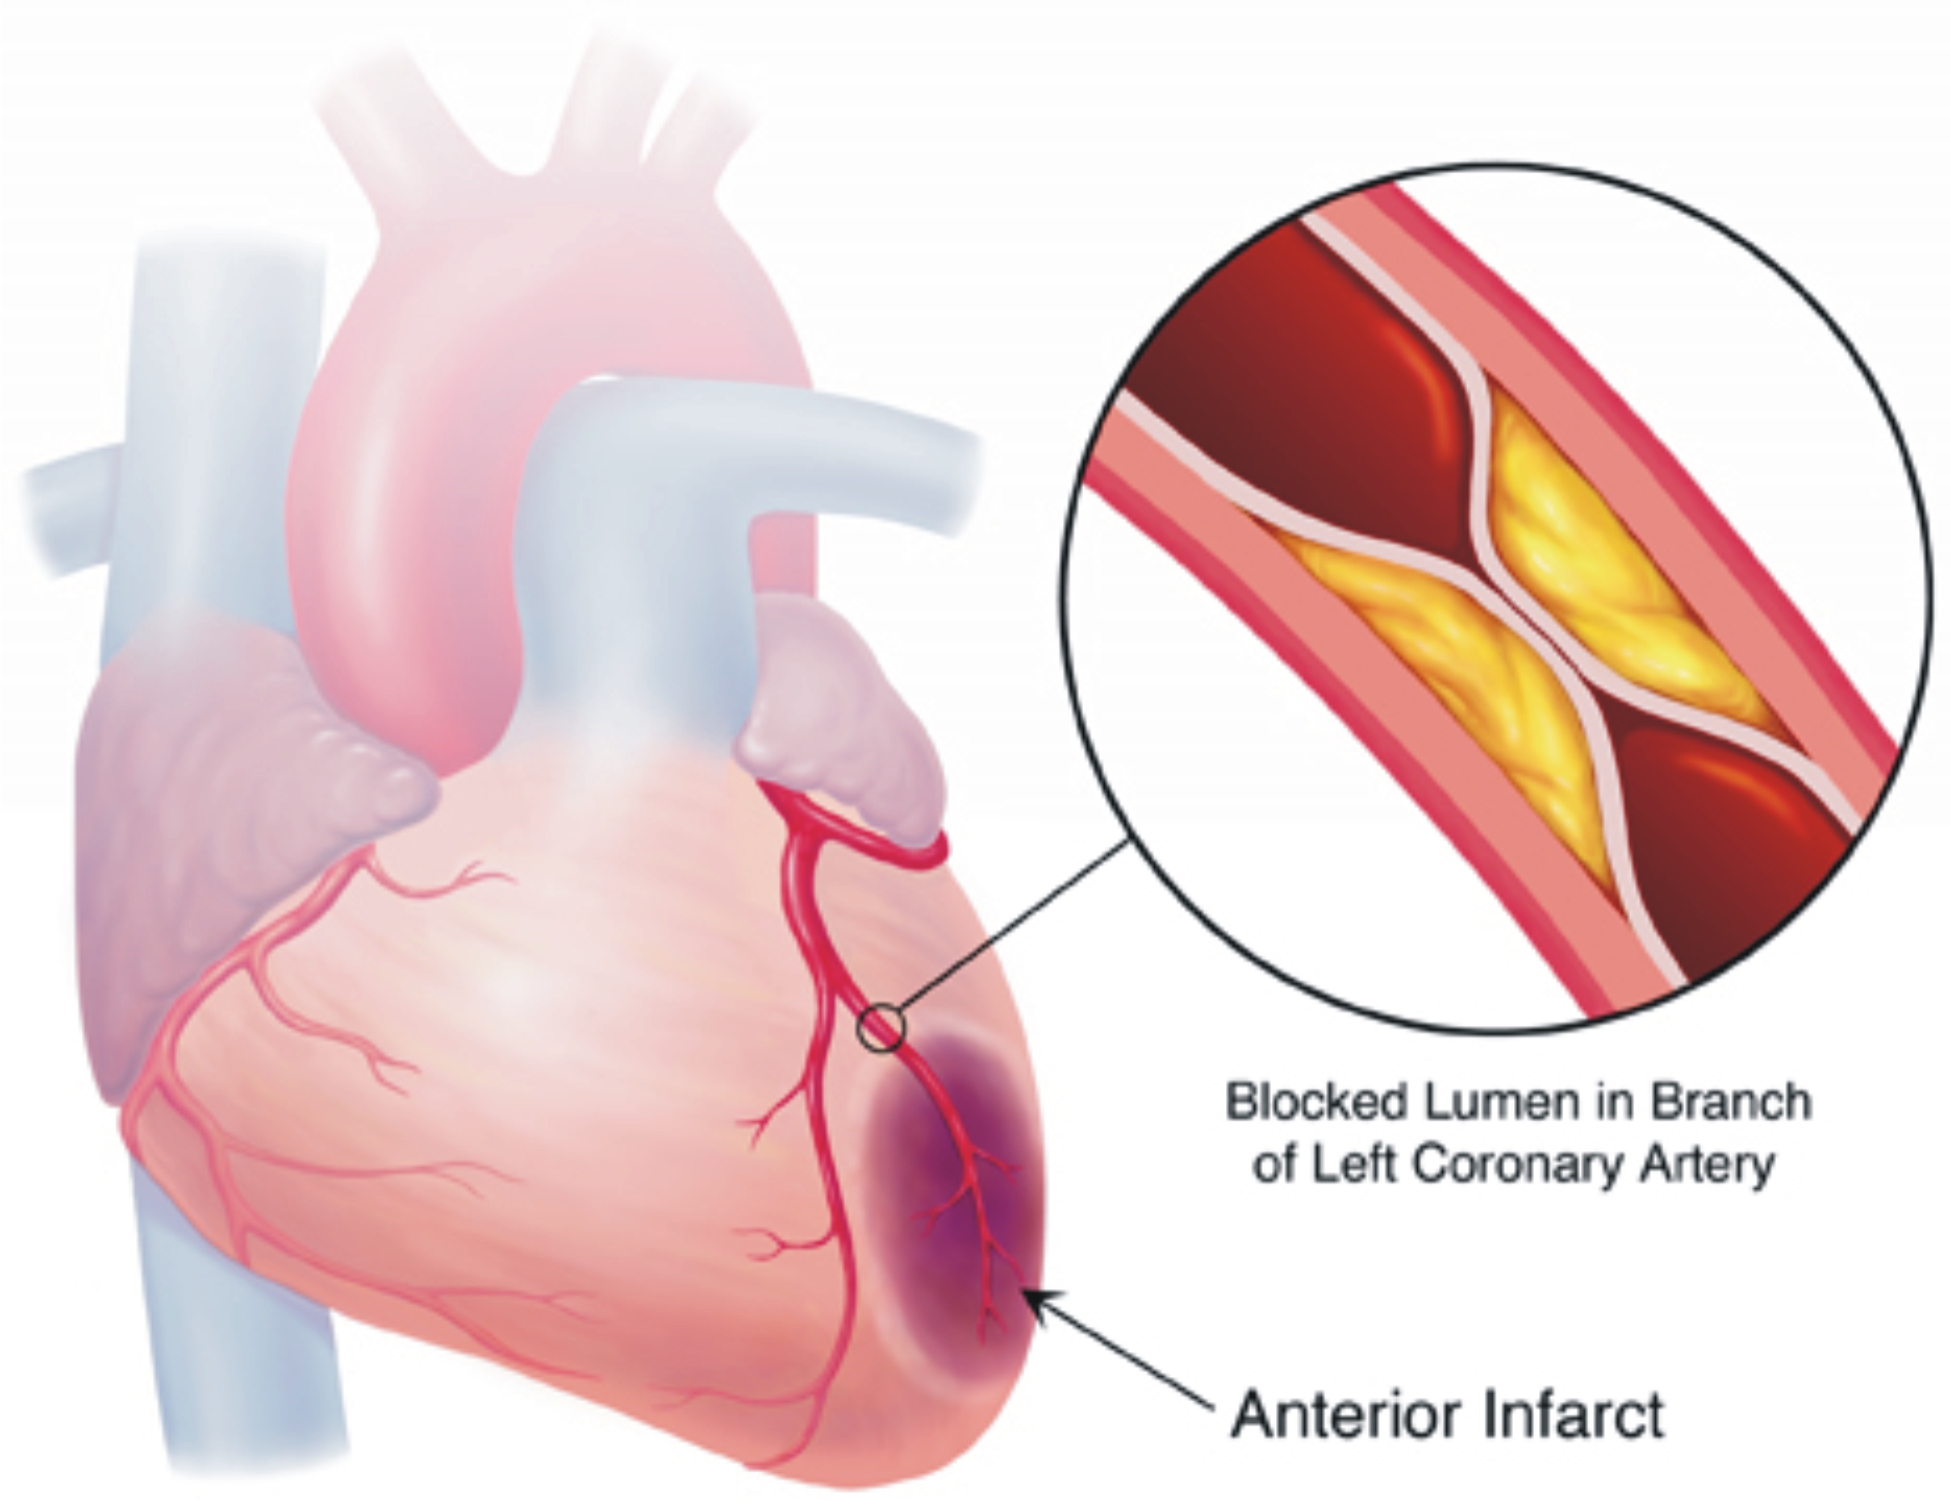

Хроническая окклюзия артерий: причины, симптомы и лечение